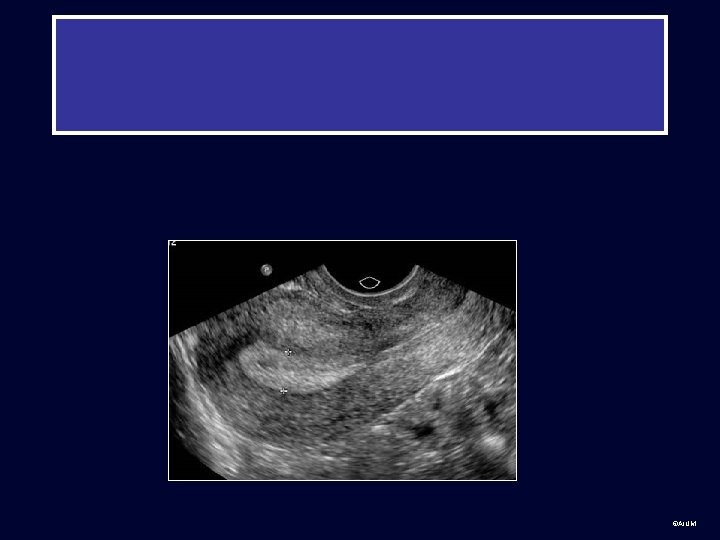

Practice cases for students: Normal and abnormal • Transabdominal, transvaginal or can’t tell? • Body part? • Normal or abnormal (provide diagnosis or Ddx if possible) ©AIUM

Group 2 ©AIUM

©AIUM

• ©AIUM